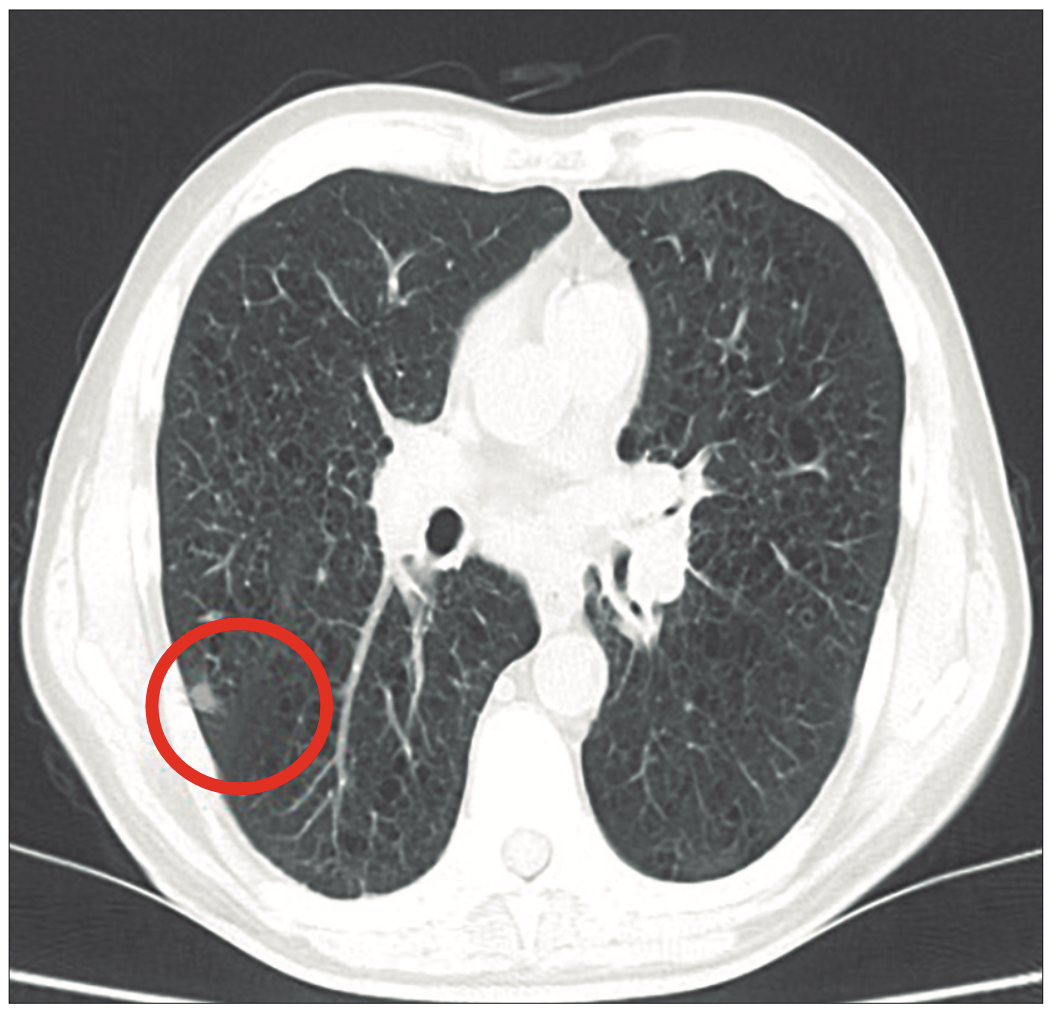

Paciente masculino de 64 años con antecedentes patológicos de cirrosis por alcohol, hipertensión arterial (HTA), y antecedentes tóxicos de consumo de tabaco (80 paquetes año) y alcohol (200 gr/día desde hace 20 años). Consulta en guardia general por dolor abdominal tipo cólico en el flanco derecho, de 72 horas de evolución, que irradia hacia mesogastrio. Se acompaña de vómitos biliosos, distensión abdominal y cinco deposiciones diarias Bristol 7 sin sangre, moco, ni pus. El dolor abdominal y la diarrea ceden con la administración de propinox clorhidrato y tratamiento nutricional. A los 15 días consulta por pérdida de peso y trastorno del sensorio asociado a hiponatremia severa (< 120 mEq/l), quedando internado con sospecha de cirrosis descompensada, en el contexto de una cirrosis de origen etílico confirmada por FibroScam CAP F4, con presencia de várices esofágicas pequeñas. Los exámenes complementarios incluyen una resonancia magnética nuclear (RMN) de abdomen y pelvis, que revela lesiones focales en el segmento VI del hígado, atribuibles a implantes metastásicos (Figuras 1 y 2).

Figura 1.

Figura 2.

Además, se identifican lesiones focales en las glándulas suprarrenales, implantes óseos y peritoneales, así como adenomegalias precavas y a la derecha del origen del tronco celíaco. Laboratorio: TSH 0,98 µUI/Ml; T3 1,04 ng/ml; T4 1,22 ng/dl. Ionograma urinario de 24 horas: Na 65 mEq /24 horas, K 40 mEq/24 horas, Cl 180 mEq/24 horas. Ecocardiograma: índice de masa del ventrículo izquierdo (INMI) 65 gr/m2. Examen físico: sin edemas, ni ascitis, ni ingurgitación yugular. Este caso muestra una extensión significativa de la enfermedad metastásica, con implicancias para el manejo y pronóstico del paciente. Se realizó tratamiento con reposición de sodio siguiendo protocolos actualizados, observándose una mejoría clínica que permitió el alta médica. Posteriormente, continuó con seguimiento ambulatorio, y falleció a los pocos meses por shock hipovolémico secundario a hemorragia digestiva variceal.